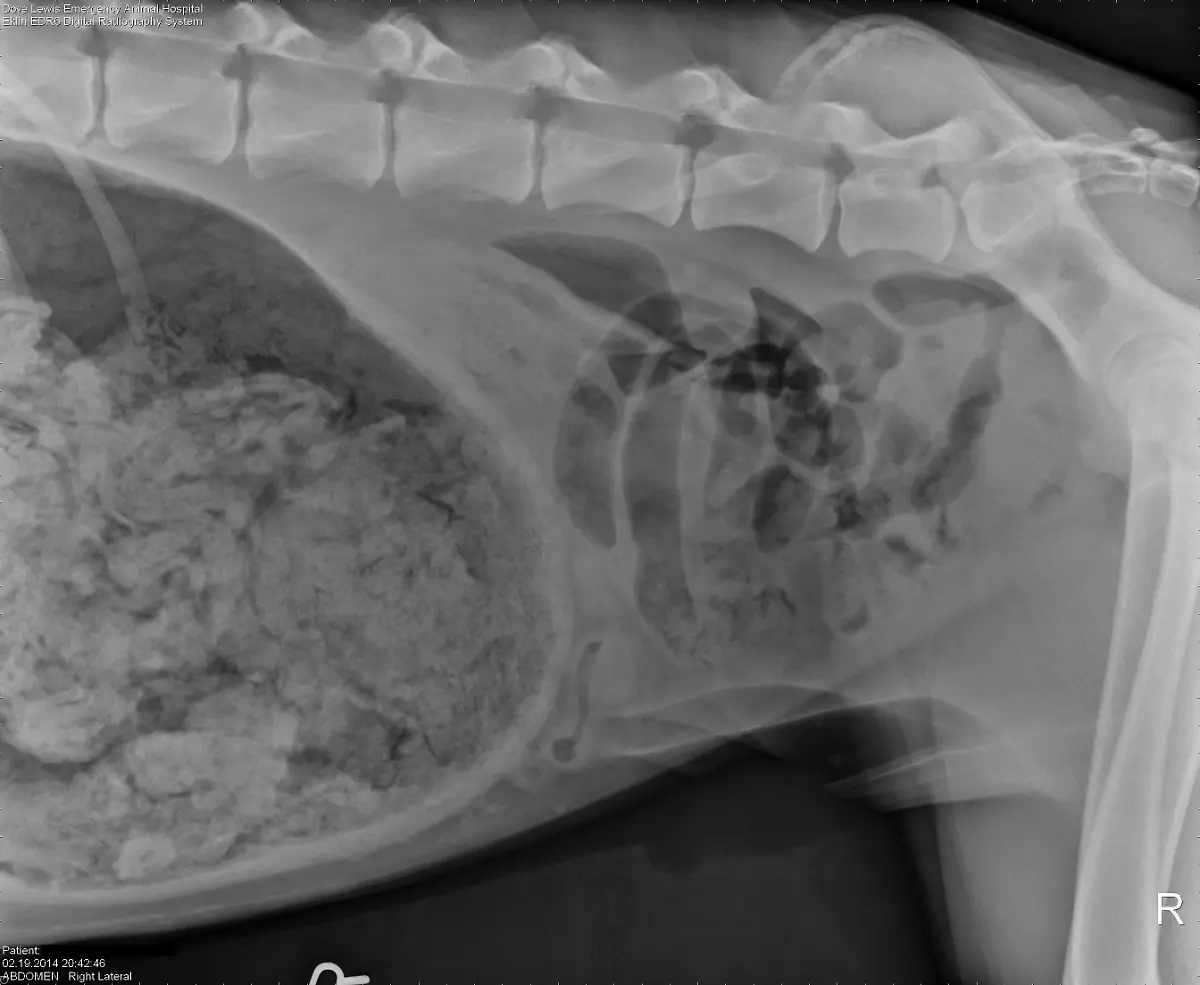

Socken, Kieselsteine, Außerirdische - Röntgenbilder von Mägen US-amerikanischer Haustiere zeigen die skurrilsten Gegenstände. Eine Zeitschrift zeichnet jedes Jahr die außergewöhnlichsten Aufnahmen aus.